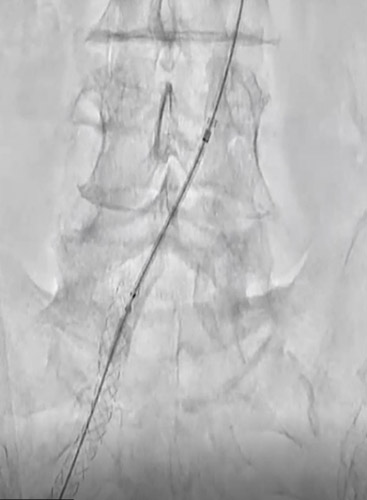

CIAにR2P Misago 9-40mmを留置。ステントproximalはCIA入口部ジャストに合わせたが、R2P Misagoはリリース時に位置ずれしにくく狙った位置に留置できた(図7)。

その後、Senri 6-40mmでポスト拡張。動脈瘤部も造影剤の染み出しもなく終了した(図8)。